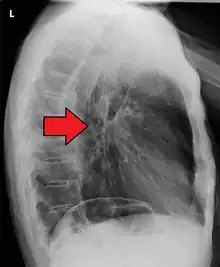

Esophageal cancer as shown by a filling defect during an upper GI series

Although an occlusive tumor may be suspected on a barium swallow or barium meal, the diagnosis is best made with an examination using an endoscope. This involves the passing of a flexible tube with a light and camera down the esophagus and examining the wall, and is called an esophagogastroduodenoscopy. Biopsies taken of suspicious lesions are then examined histologically for signs of malignancy.